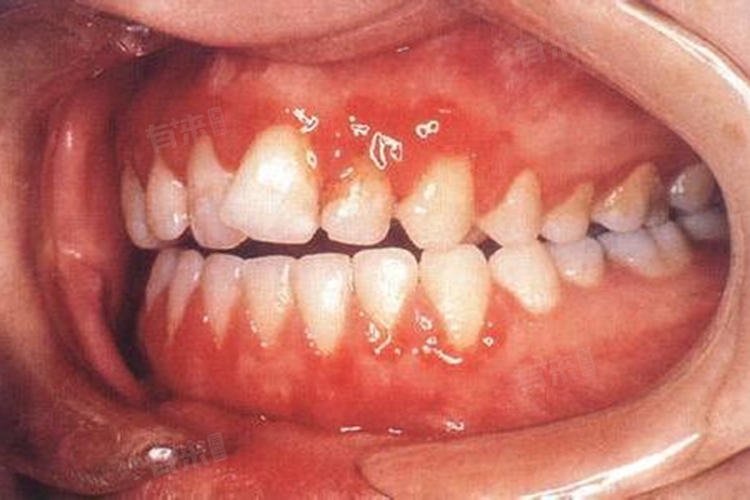

4、菌斑性龈炎:此病是牙龈组织发炎的常见疾病,主要由口腔清洁不到位引起,当牙齿上形成大量的牙石、牙菌斑、食物残留等,会刺激牙龈,导致牙龈发炎、红肿、出血,严重时可引发牙龈溃烂。

5、腐败坏死性牙龈炎:腐败坏死性牙龈炎是一种较为严重的牙龈疾病,主要表现为牙龈红肿伴出血,牙龈边缘腐烂,有灰白色假膜覆盖。腐败坏死性牙龈炎的疼痛剧烈,且口腔有恶臭,对患者的日常生活造成严重影响。